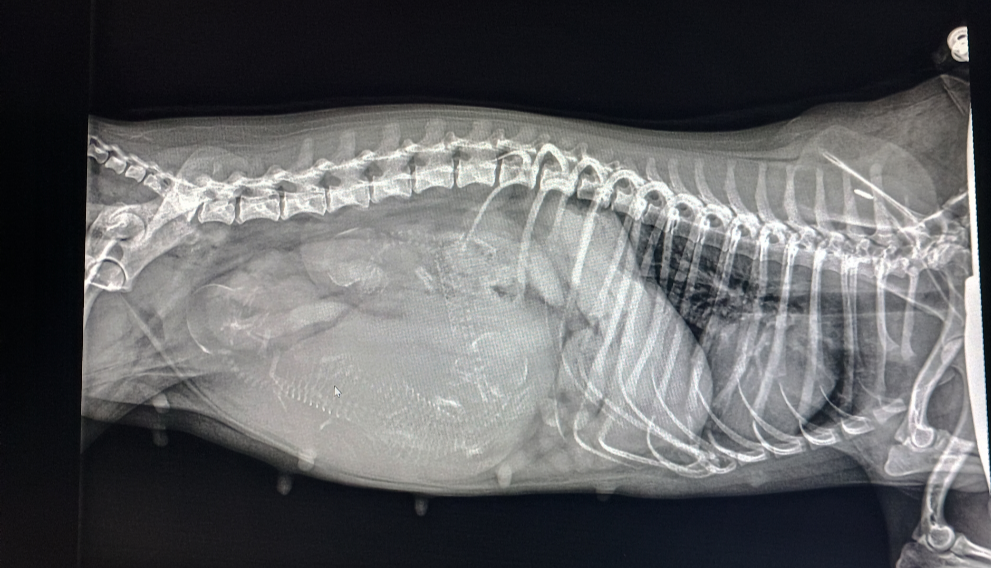

Ich begleite euch auch gern zum Röntgen eures Tierarztes persönlich (Berlin) oder auch per Live Video Schalte Weltweit, um die Lage der Welpen festzustellen und ob alles okay ist. Desweiteren bin ich über die ganze Zeit per WhatsApp erreichbar für euch bis zur Geburt. Ihr könnt mir jederzeit eure Fragen stellen, die ihr habt.

Röntgen sollte man ab dem 50-57. Trächtigkeitstag, um auch zu sehen, wie gross sie sind, wie viele es sind und ob sie durch ein womöglich zu enges Becken der Hündin passen. Auch die Lage ist entscheidend für eine unkomplizierte Geburt. All diese Risiken werden durch Röntgen vor der Geburt minimiert und ihr wisst was auf euch zukommt bei der Geburt.